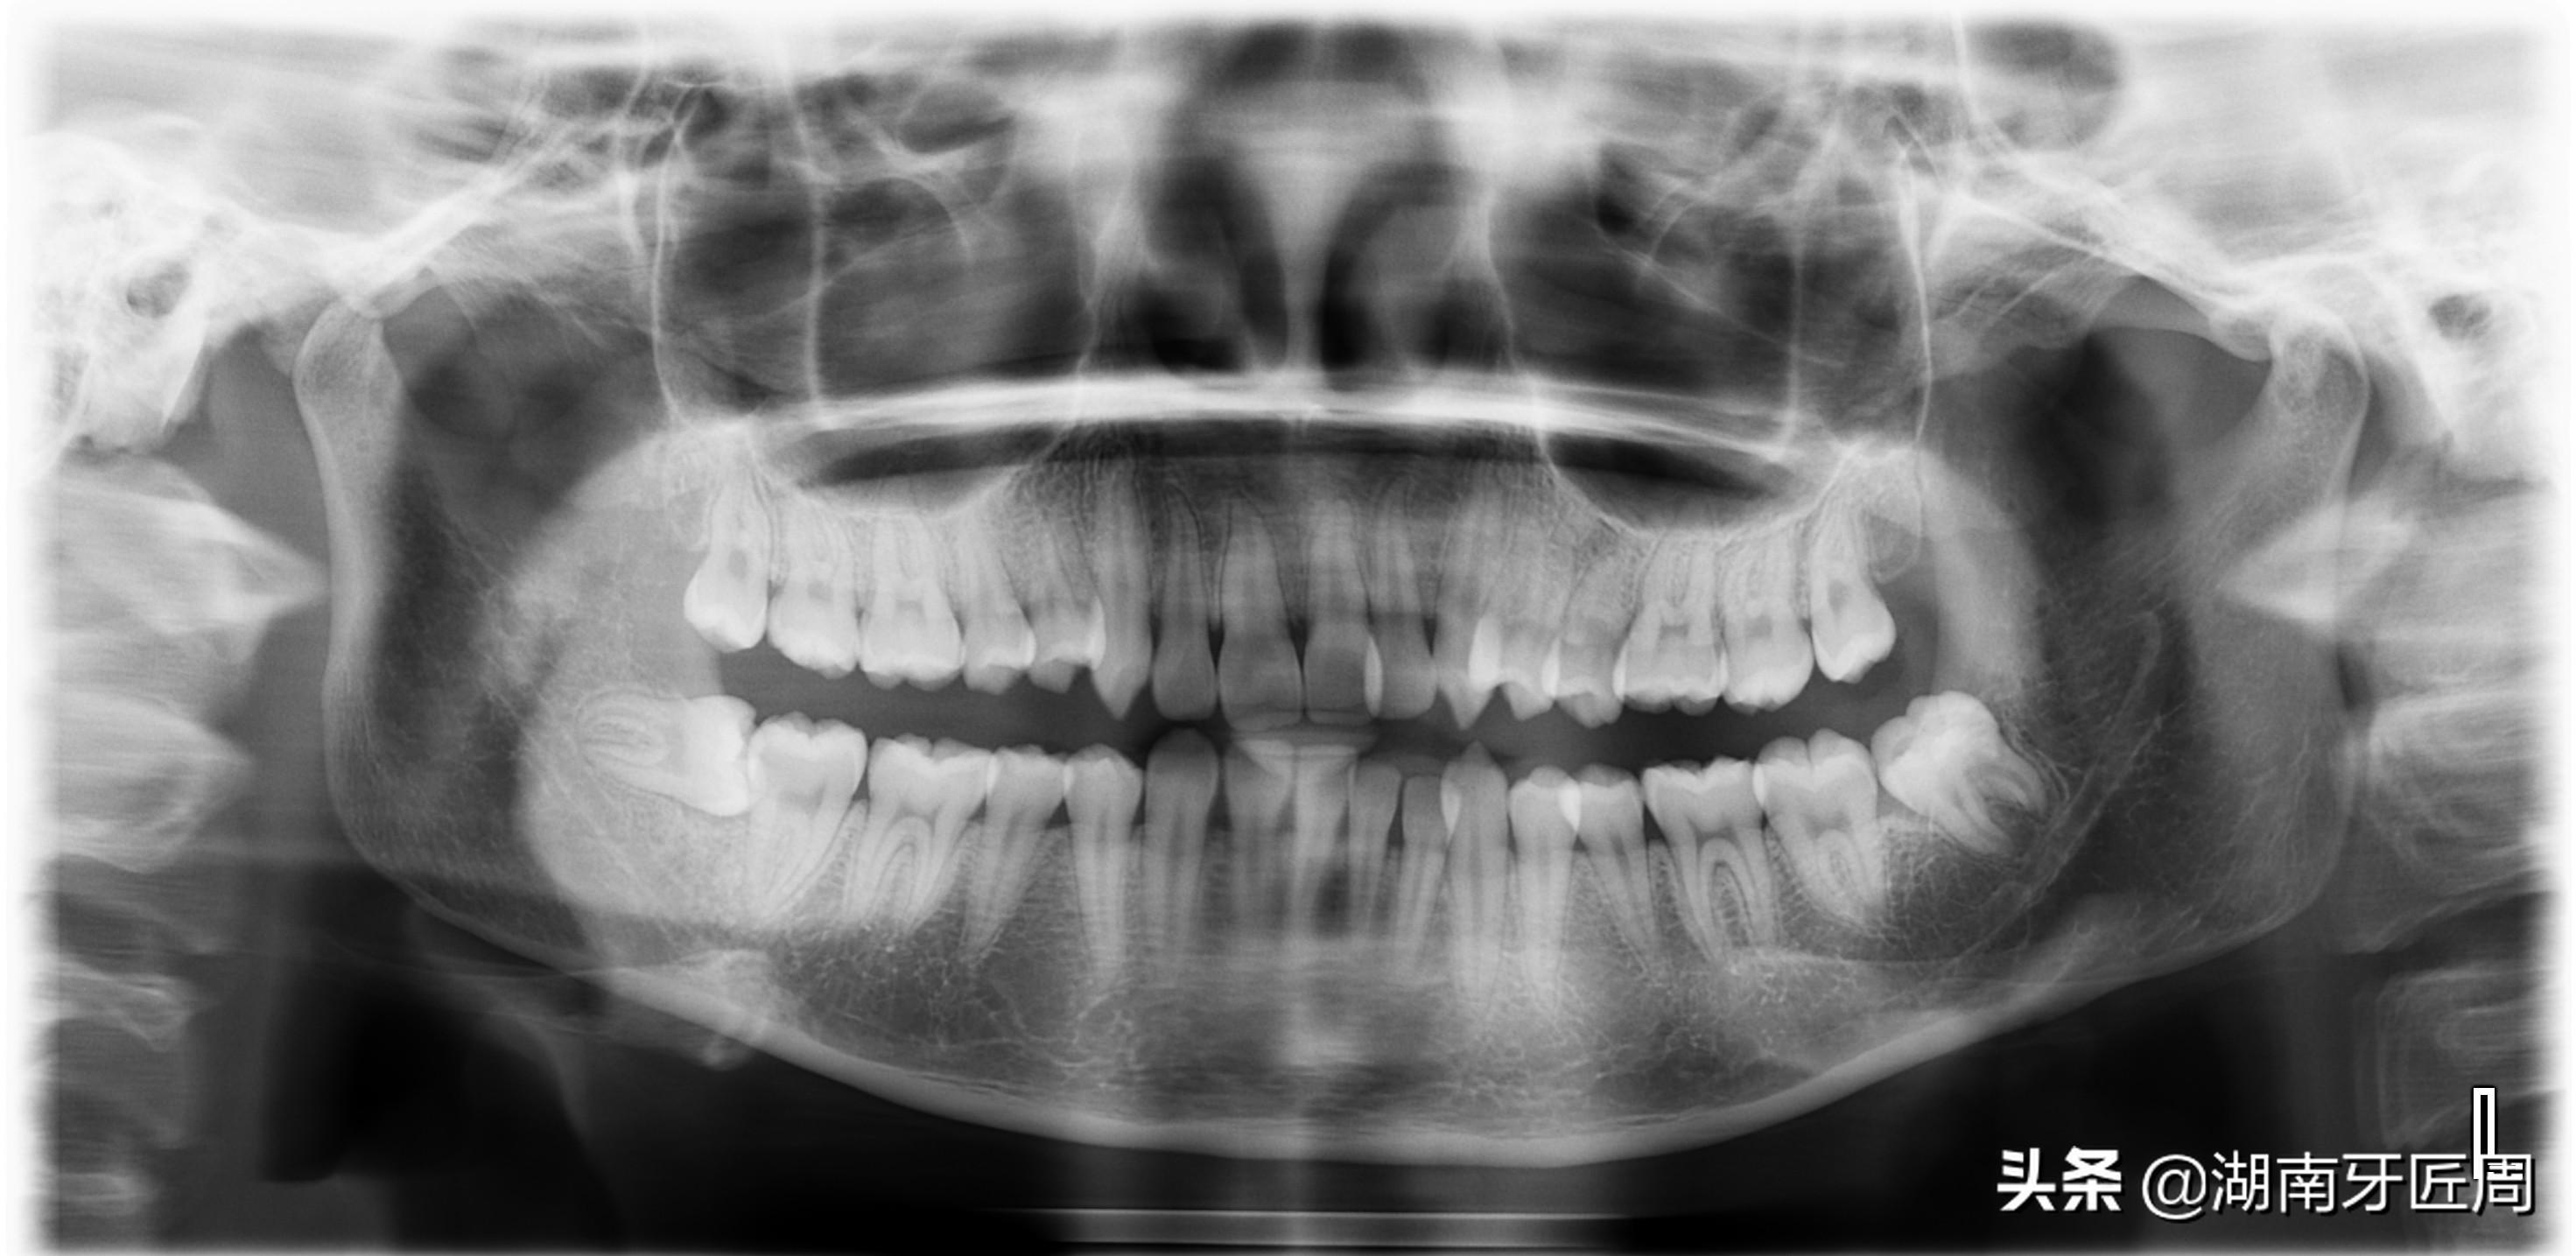

图片7两侧下颌智齿阻生

图片8